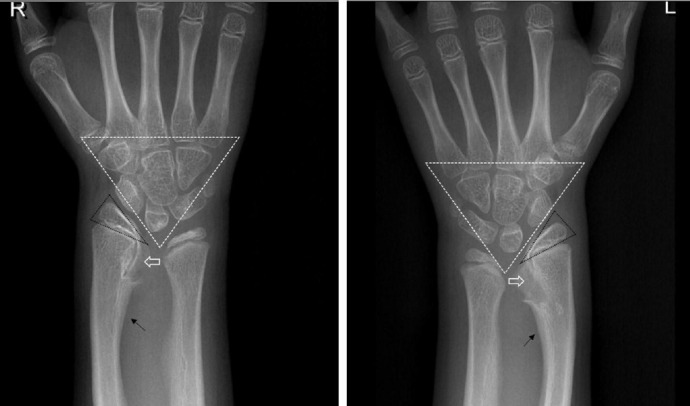

在一名伴有生长激素缺乏症的 Leri-Weill 软骨发育不良症患者体内发现一种新型 SHOX 基因突变。

Identification of a novel mutation of the SHOX gene in a patient with Leri-Weill dyschondrosteosis accompanied by growth hormone deficiency.